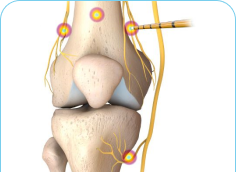

Radiofrequency Ablation may be used in cervical, thoracic, and lumbar spine. It can also be used in the sacroiliac joint and peripheral nerves, where the procedure is employed to reduce pain from the arthritic joints. Radiofrequency Ablation is a technique that employs heat to disable the pain-transmitting nerves in the spine.

The procedure is very safe and is only used on sensory nerves that transmit pain impulses. There is no risk of paralysis or weakness from this procedure. Radiofrequency Ablation uses heat to disable the pain-transmitting nerves in the spine. The process is analogous to microwave ovens that use microwave energy to heat food. Radiofrequency Energy is transmitted to the tip of a needle where it is converted to heat, which is applied directly to the nerve fibers. Once the nerves undergo this heat treatment, they slowly stop transmitting pain.